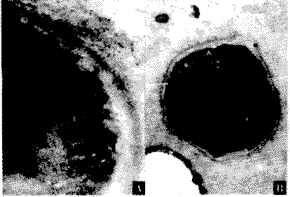

2.将FGF100ng/ml换液时加入细胞培养液,免疫电镜显示细胞膜外表面有明显胶金颗粒黏附,而对照组则较少(图3,4,其中A及B分别为高倍和低倍电镜所示)。

图3 用FGF100ng/ml作用于培养细胞,免疫组织化学电镜显示实验组细胞膜

表面有明显的胶金颗粒黏附(A为高倍×60 000×2.5,B为低倍×10 000×2.5

图4 对照组细胞膜表面胶金颗粒很少(A为高倍×60 000×2.5,B为低倍×10 000×2.5)